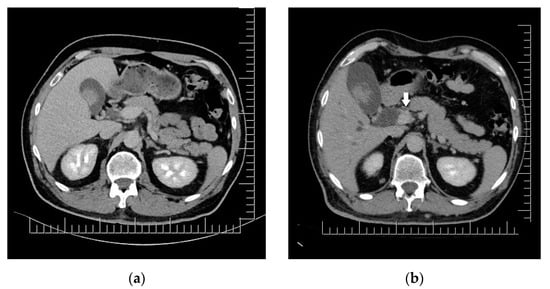

2. Case Presentation